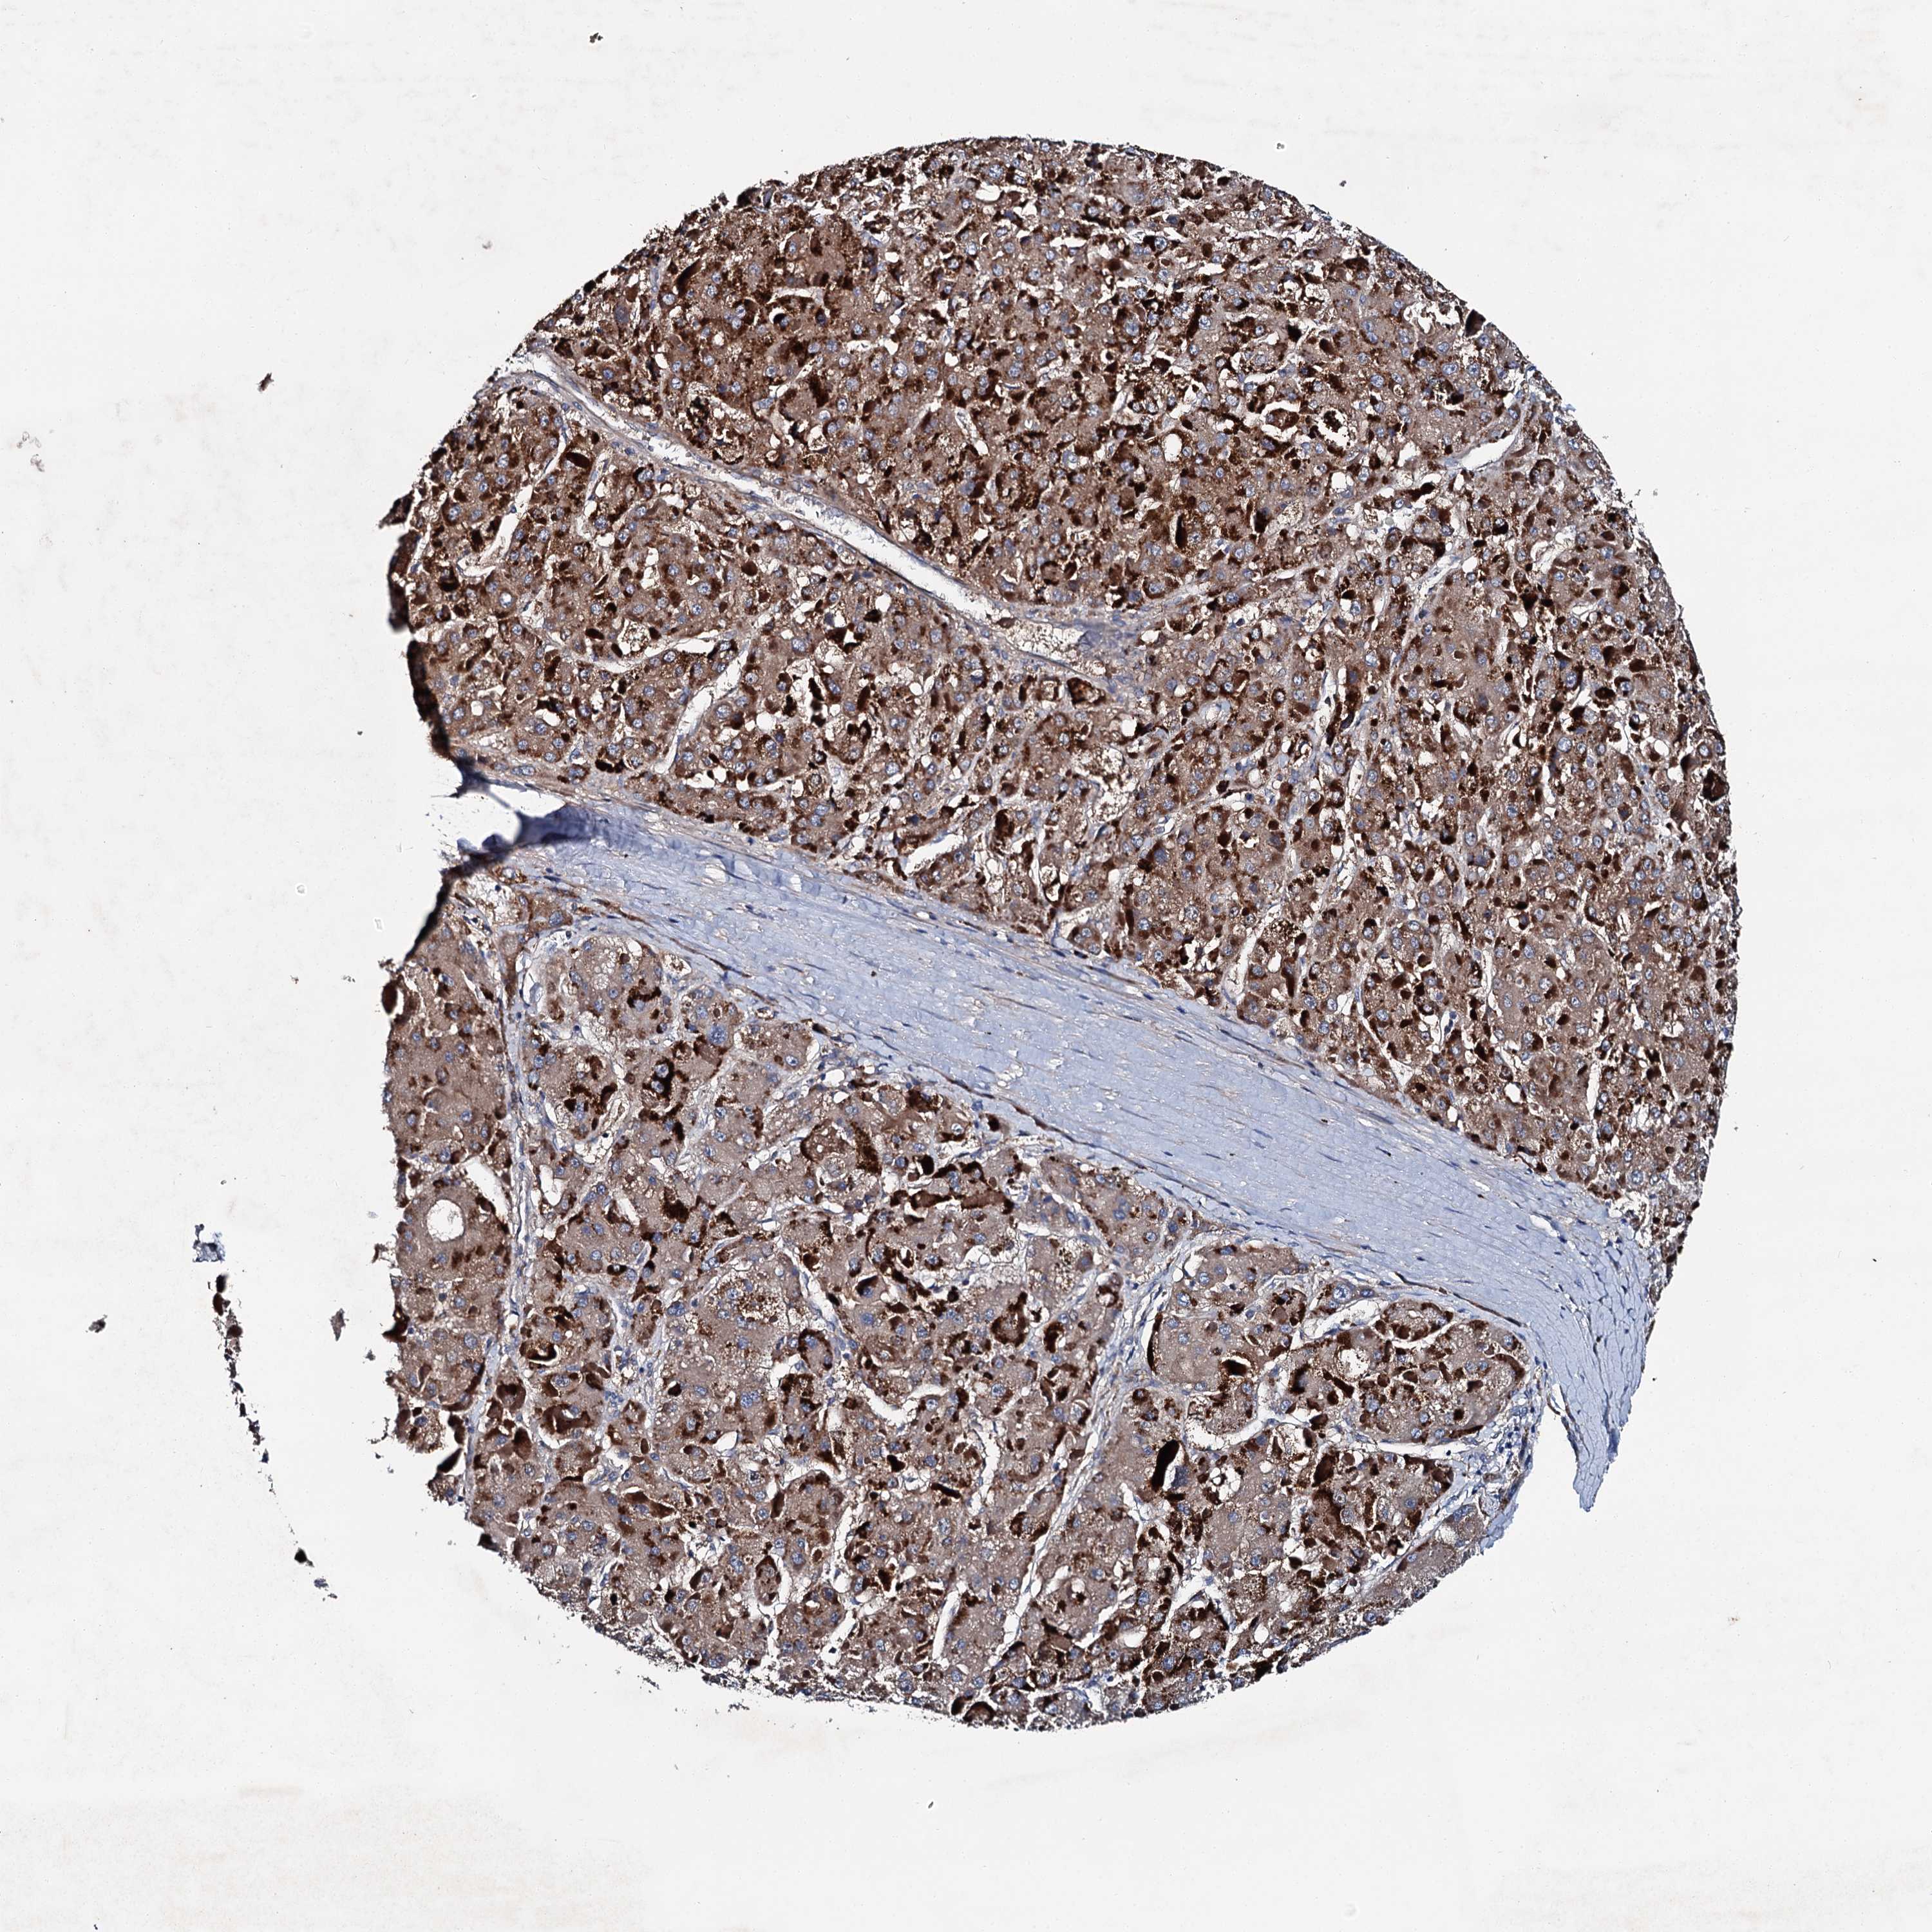

LIVER CANCER - Protein expressioni

A mouse-over function shows sample information and annotation data. Click on an image to view it in a full screen mode. Samples can be filtered based on level of antibody staining by selecting one or several of the following categories: high, medium, low and not detected. The assay and annotation is described here.

Note that samples used for immunohistochemistry by the Human Protein Atlas do not correspond to samples in the TCGA dataset.

Antibody stainingi

Antibody staining in the annotated cell types in the current human tissue is reported as not detected, low, medium, or high, based on conventional immunohistochemistry profiling in selected tissues. This score is based on the combination of the staining intensity and fraction of stained cells.

Each image is clickable and will lead to virtual microscopy that enables deeper exploration of all samples and also displays staining intensity scores, fraction scores and subcellular localization as well as patient and tissue information for each sample.

Antibody HPA039390

Staining

High

Medium

Low

Not detected

Intensity

Strong

Moderate

Weak

Negative

Quantity

>75%

75%-25%

<25%

None

Location

Nuclear

Cytoplasmic/membranous

Cytoplasmic/membranous,nuclear

Cholangiocarcinoma

Carcinoma, Hepatocellular, NOS